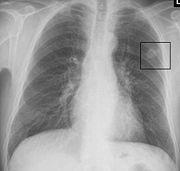

Performing a chest x-ray is the first step if a patient reports symptoms that may be suggestive of lung cancer. This may reveal an obvious mass, widening of the mediastinum (suggestive of spread to lymph nodes there), atelectasis (collapse), consolidation (pneumonia), or pleural effusion. If there are no x-ray findings but the suspicion is high (such as a heavy smoker with blood-stained sputum), bronchoscopy and/or a CT scan may provide the necessary information. Bronchoscopy or CT-guided biopsy is often used to identify the tumor type.

The differential diagnosis for patients who present with abnormalities on chest x-ray includes lung cancer, as well as nonmalignant diseases. These include infectious causes such as tuberculosis or pneumonia, or inflammatory conditions such as sarcoidosis. These diseases can result in mediastinal lymphadenopathy or lung nodules, and sometimes mimic lung cancers.